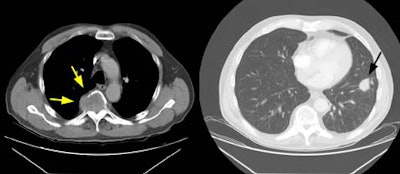

Example 2: This patient is an example of a false negative CT for hilar nodal metastases even when applying the suggested new criterion. The patient had a peripheral adenocarcinoma in the left upper lobe (black arrows). The left hilar node (yellow arrows) is not pathologic by size criteria, nor does it exhibit a convex margin with the adjacent lung parenchyma. This is a normal node by CT, however, at histopathologic analysis the node was positive for malignant cells.

NOTE: Click image to enlarge